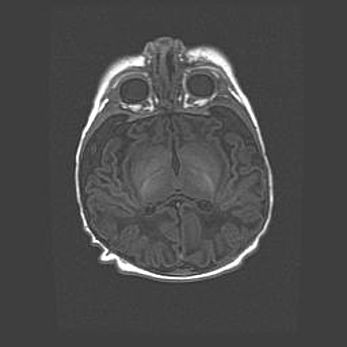

Церебральная ишемия II.

Возраст: 5 дней

Вес: 3400 г

Пол: женский

Окружность головы: 35 см

Срок гестации: 39 недель

Церебральная ишемия – это заболевание, характеризующееся недостаточностью (гипоксией) либо полным прекращением (аноксией) снабжения мозга кислородом по причине закупорки одного или нескольких сосудов. Это приводит к  что метаболическим расстройствам различной степени тяжести в тканях головного мозга, развитию коагуляционных некрозов и гибели нейронов.